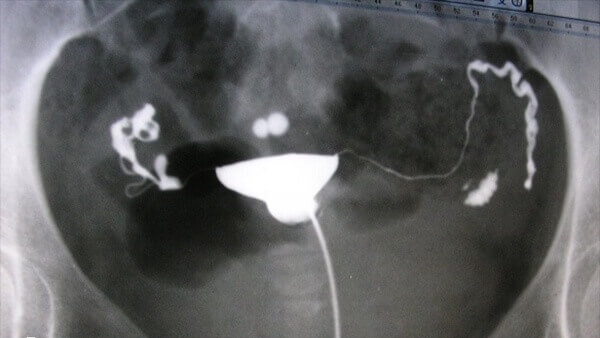

人工授精只适用于卵巢功能正常输卵管通畅的女性,如果女性输卵管异常,那么都是会影响人工授精的成功率的,进而导致胚胎难以着床;

人工授精前一半需要使用大量的促排药物,并且还需要用细管将精子送到女性输卵管位置,一旦操作不当就会对女性的身体造成极大的伤害,增加子宫和输卵管感染的几率。